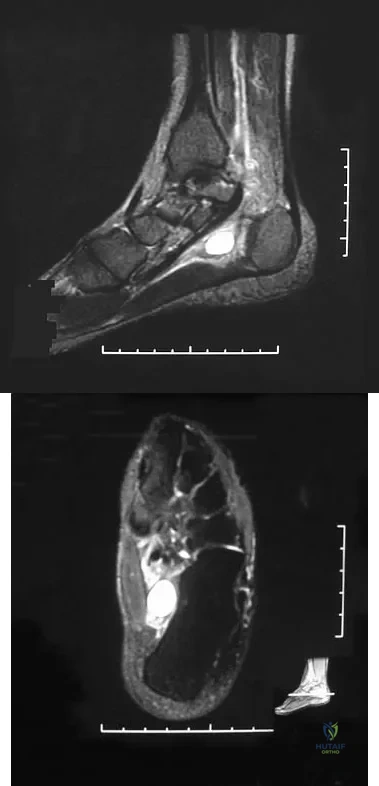

Question 40

A 37-year-old woman has had intermittent paresthesias and numbness in the plantar foot for the past 6 months. She reports that the symptoms are worse with activity, and the paresthesias are beginning to awaken her at night. MRI scans are shown in Figures 6a and 6b. What is the most likely diagnosis?

Explanation